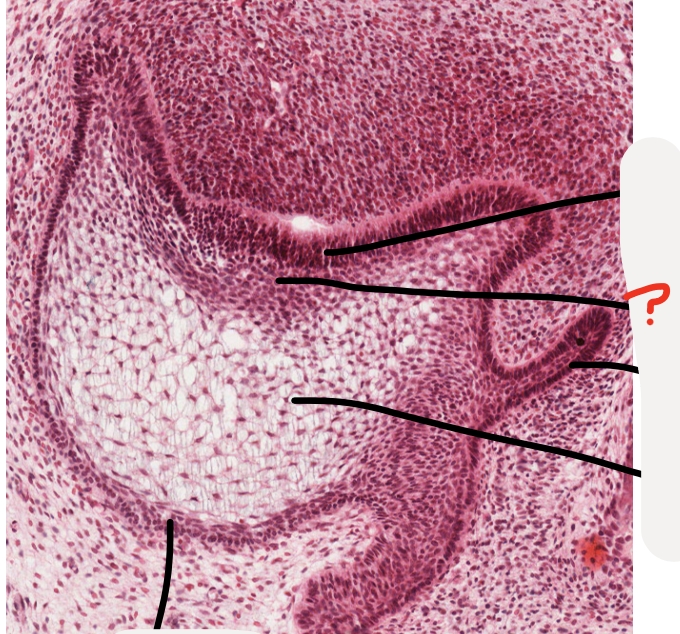

Q

what stage is this tooth germ?

cap stage

A

dental papilla